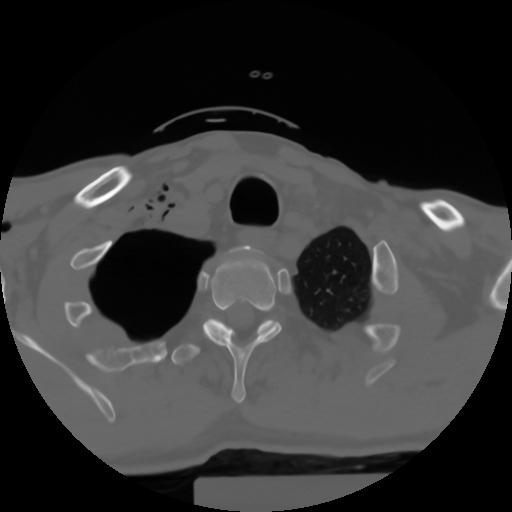

10 P.BLANDAS,,Axial,2.0,P.BLANDAS,,